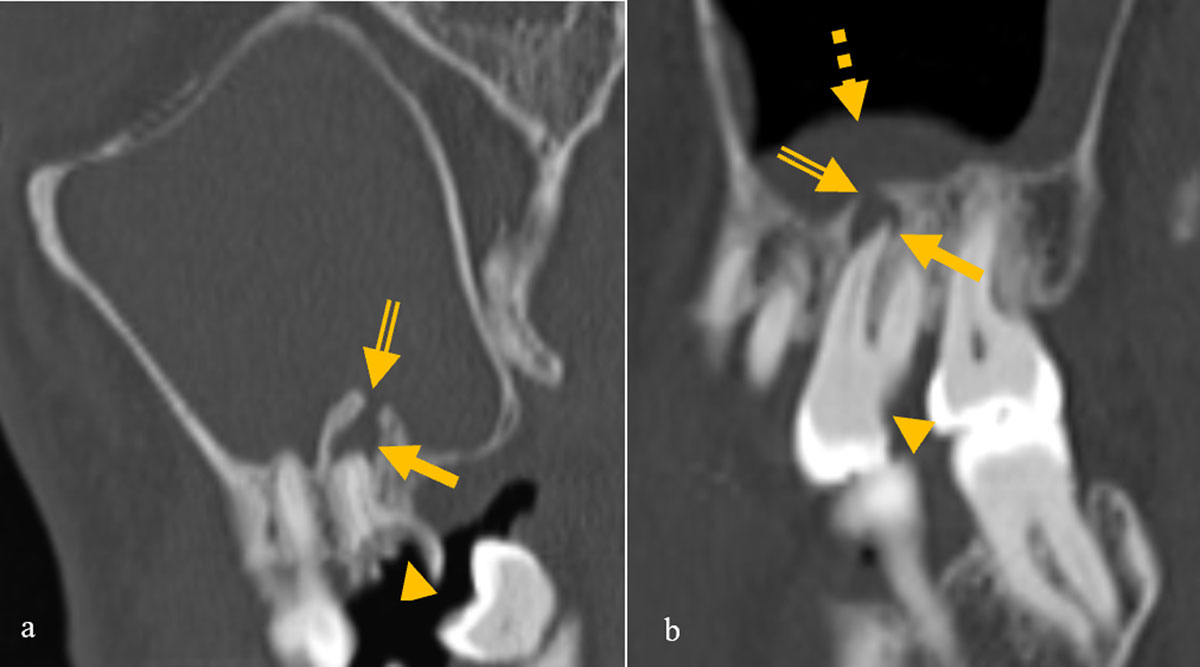

Figure 3

Images of two different patients showing dehiscence of the floor of the maxillary sinus (double lined arrow) and mucosal thickening and the causative diseased tooth with caries (arrowhead) and periapical lucency (arrow).